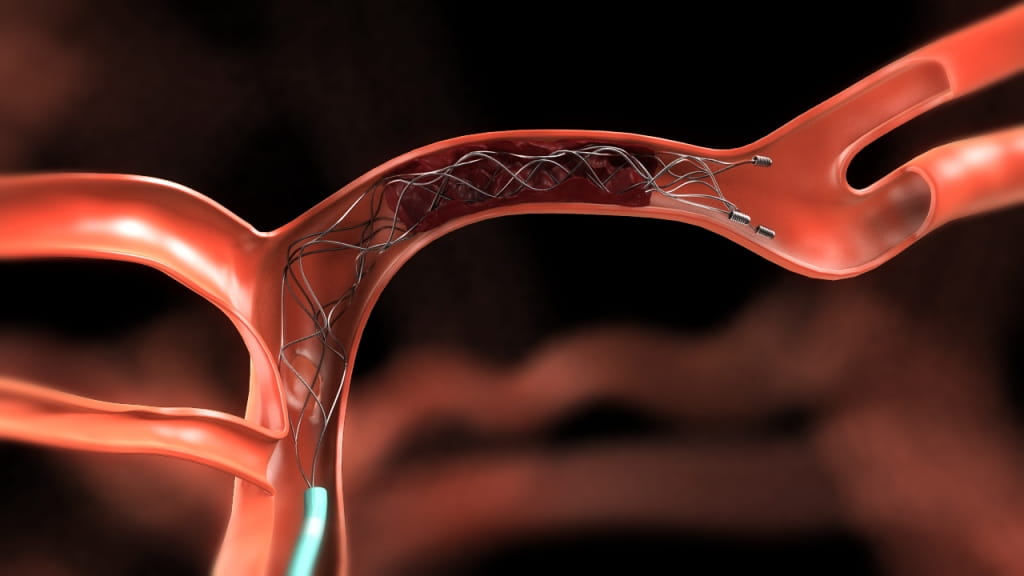

Less sophisticated devices tested previously produced disappointing results in clinical trials. But the new studies tested more modern devices such as a retrievable stent, a tiny wire cage attached to a catheter that is threaded through an artery in the groin to the blocked artery in the brain. The stent opens and traps the clot, allowing doctors to extract the clot and reopen the artery nearly every time.

Image courtesy of Covidien